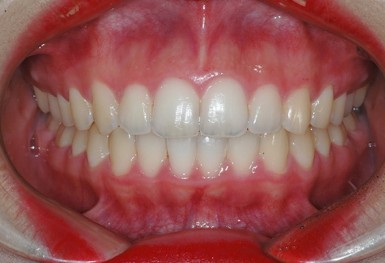

심한 덧니